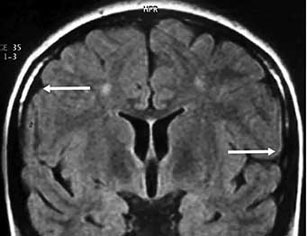

Se realizan los siguientes estudios encontrando los hallazgos a continuación reportados. Los estudios de imagen realizados durante su evolución fueron resonancia magnética de cráneo (RMN) de 0.5 UT donde solo se identificó atrofia cortical difusa, sin ningún otro hallazgo (figura 2); así como electroencefalograma (EEG) con previa colocación de electrodos mediante el sistema internacional 20-20, el cual, realizado con deprivación de sueño, mostró ritmo de fondo delta entremezclado con theta, identificando durante el trazo ondas agudas occipitales y paroxismos generalizados de polipuntas. El tamiz metabólico ampliado fue normal y el resultado de la biopsia de piel de regiones axilares identificó cuerpos de inclusión intracitoplásmicos PAS positivo a nivel de células epiteliales de glándulas sudoríparas, identificando los cuerpos de Lafora (figura 3).